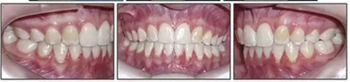

治療的總體目標得以實現(xiàn)(圖8)??傊委煏r間為36個月。面部方面表現(xiàn)出充分的唇閉合和愉快的微笑。切牙運動后有一些唇縮回。覆蓋和覆合良好,并且上下牙弓相協(xié)調(diào)(圖9)。I類磨牙關(guān)系得以實現(xiàn)。左側(cè)后牙反合得以矯正。下頜第二磨牙成功直立。

6年后治療結(jié)果保持穩(wěn)定(圖11,圖12 ; 圖13)??梢杂^察到穩(wěn)定的間隙關(guān)閉,正常的覆蓋和覆合,上下牙中線一致,微笑美觀。建議完美替代了拔除的側(cè)切牙。正畸治療后進行牙齒美白。